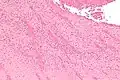

Low magnification micrograph showing laminations in a thrombus in a fatal pulmonary embolism. H&E stain. -

Intermediate magnification micrograph showing laminations in a thrombus in a fatal pulmonary embolism. H&E stain. -

High magnification micrograph showing laminations in a thrombus in a fatal pulmonary embolism. H&E stain.